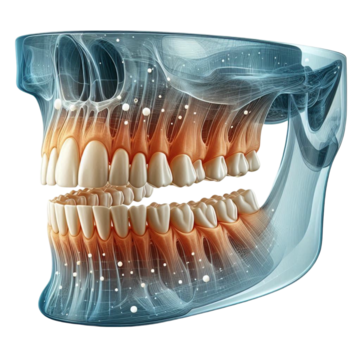

Full Mouth X-Ray (OPG)

Our advanced OPG X-ray provides a panoramic view of your entire jaw, helping in the accurate diagnosis of dental conditions. Essential for orthodontic planning, implant placement, and detecting hidden oral health issues.